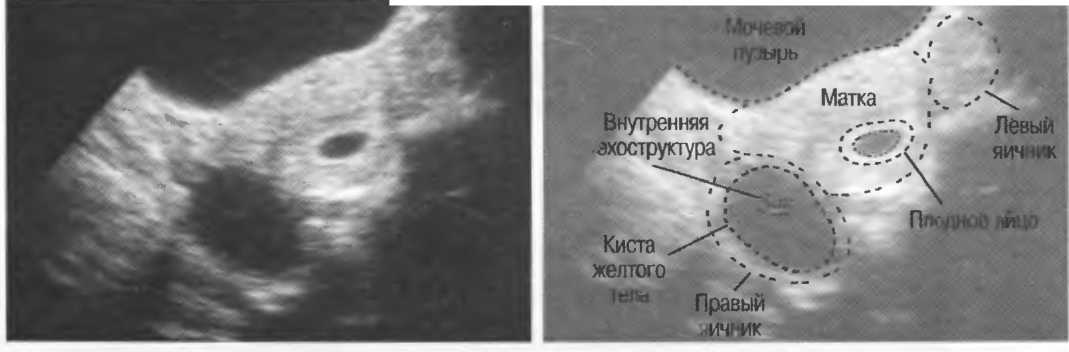

1. Подготовка

Пациент не должен пить и есть в течение 8 ч перед исследованием. Если жидкость необходима для предотвращения дегидратации, можно давать пациенту только воду. При острой симптоматике исследование можно проводить без подготовки. Детям, если позволяют клинические условия, пища и вода не даются в течение 3 ч до исследования.

При более углубленном исследовании, если нет клинических противопоказаний, может быть полезным дополнительный прием воды, особенно при исследовании поджелудочной железы, нижних отделов живота и таза.

2. Положение пациента. Пациент может лежать в удобной позе на спине. Под голову можно положить маленькую подушку, в случае выраженного напряжения передней брюшной стенки подушечку можно поместить также под колени пациента.

Намажьте живот гелем.

Пациенту разрешается дышать спокойно, однако при исследовании отдельных органов требуется задержка дыхания на вдохе.

3. Выбор датчика. Используйте датчик 3,5 МГц для взрослых и датчик 5 МГц для детей и худых взрослых. Предпочтительны конвексные или секторные датчики.

4. Установите правильный уровень общей чувствительности. Начинайте исследования, поместив датчик центрально в верхней части живота под мечевидным отростком и попросите пациента глубоко вдохнуть и задержать дыхание на вдохе.

Поверните датчик направо до того, как начнет визуализироваться печень. Отрегулируйте чувствительность, чтобы изображение имело нормальную однородную зхоструктуру. Должна быть хорошо различима высокоэхогенная линия диафрагмы сразу за задними отделами печени (рис. 27а).

Воротная и печеночные вены должны визуализироваться как трубчатые структуры с анзхогенным просветом. Стенки воротной вены высокозхогенны, но стенки печеночных вен практически не видны (рис. 276).

Рис.27а. Продольный срез. Неизмененная печень и диафрагма.